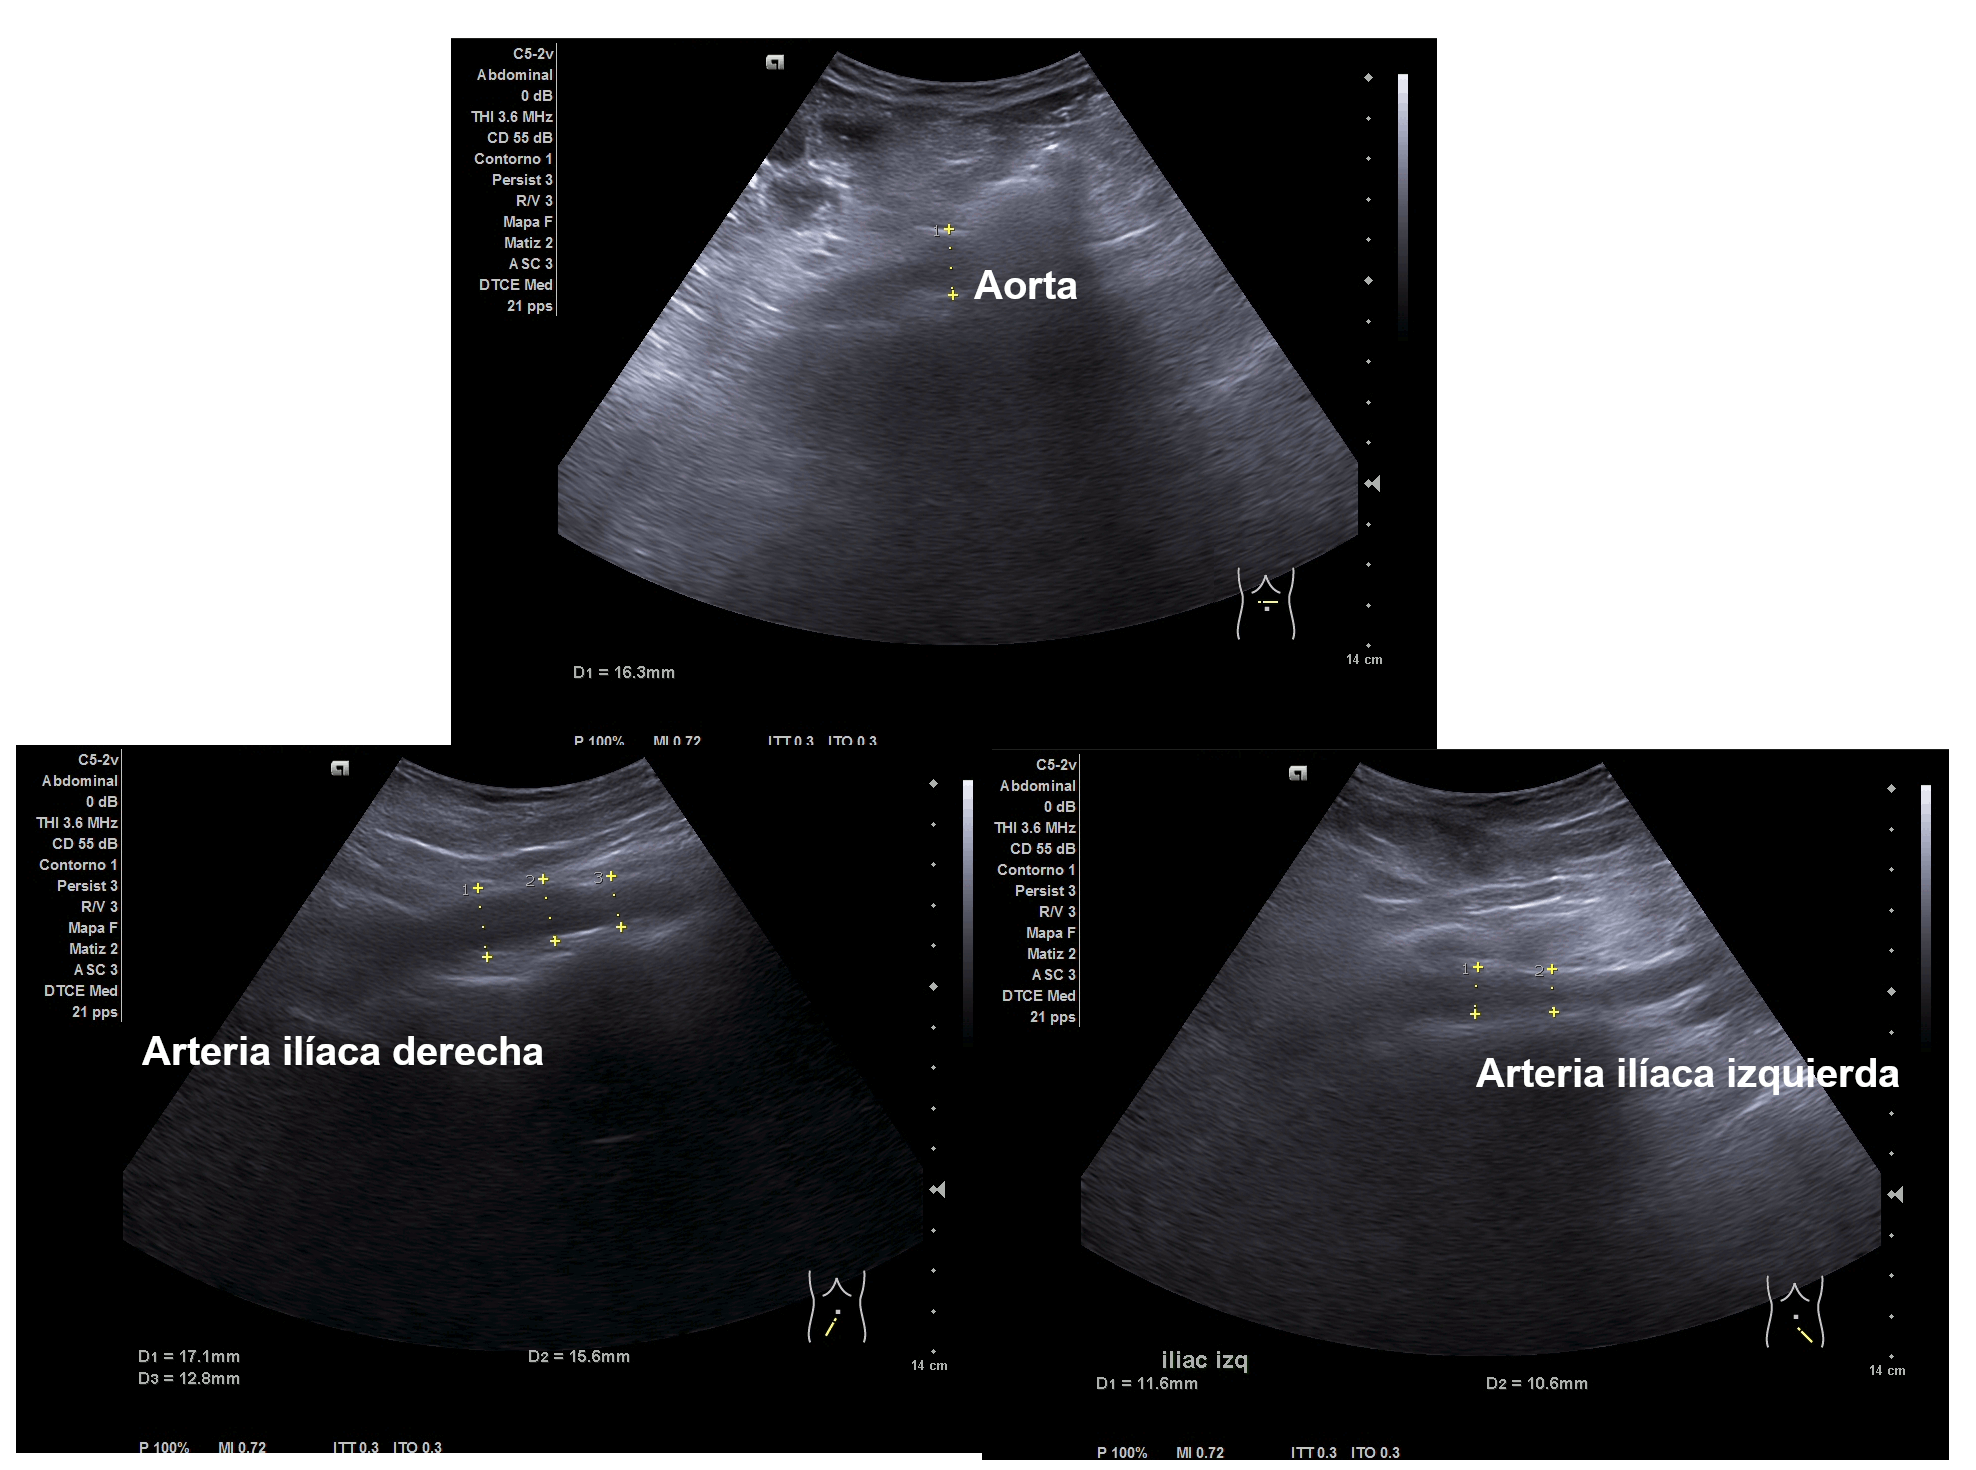

Ecografía clínica abdominal (ventana subóptima):

Parenquima hepatico sin alteraciones, vesícula biliar sin imagenes hiperecoénicas en interior. Pancreas visible en parte, sin alteraciones. Asimetría entre ambos riñones compatible variante de la normalidad RI. Llama la atención dilatación ilíaca derecha al comparar con contralateral y con aorta abdominal distal. Compatible con dilatación aneurismática ilíaca derecha.

El diagnóstico diferencial del Aneurisma Ilíaca con: Displasia fibromuscular u otra patología del tejido conectivo, lúes o tuberculosis entre otros. Toda dilatación que sobrepase el 50% del diámetro del vaso se considera aneurismática. Por la edad no se plantea el origen ateromatoso.

La ecografía en Atención Primaria se plantea en el contexto de responder a una pregunta clínica tras la anamnesis y la exploración física u otras pruebas complementarias que se precisen. A resaltar, la importancia de realizar ecografía completa siguiendo una sistemática y prestando atención tanto a variantes de la normalidad como a hallazgos patológicos. En el caso de la ecografía abdominal, es fundamental explorar los grandes vasos tanto en plano transversal como longitudinal, haciendo incapié en la división de las ilíacas.